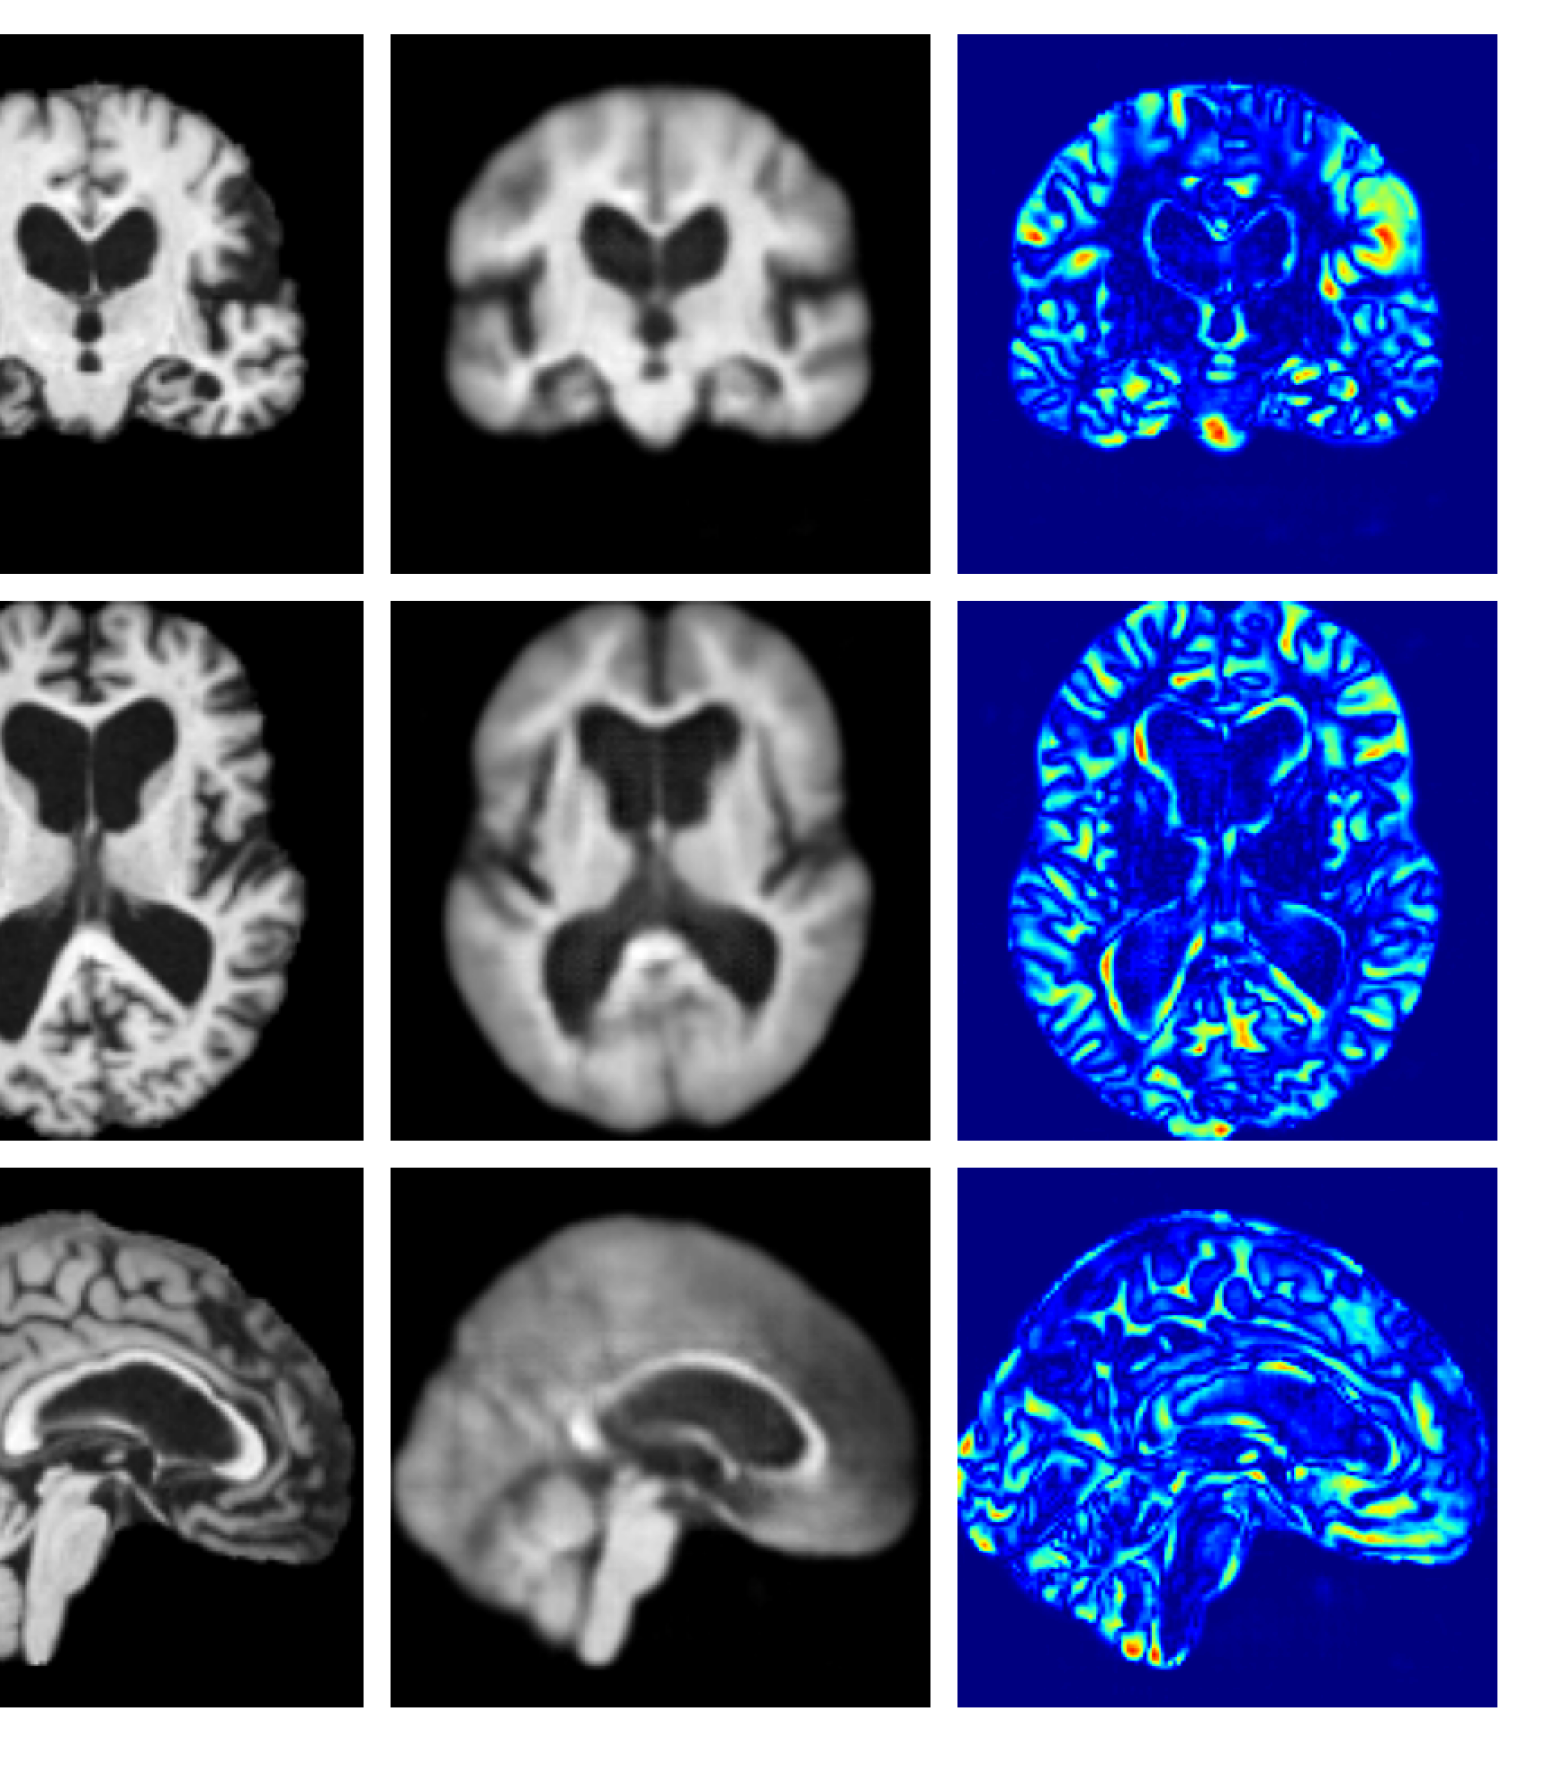

Figures 8 and 9 are enlarged versions of Figures 3 and 4 respectively, with the latter now including results from all compared methods. Figure 10 provides example reconstructions and anomaly maps for an AD subject from the ADNI disease cohort.

Figure 9: Enlarged example reconstructions and anomaly maps for a sample from the disease cohort of the XXXH dataset. The lesion region is indicated in the original image by the red box.